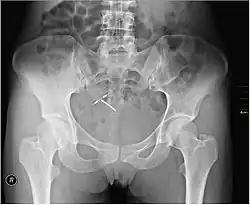

An intrauterine device (IUD), also known as an intrauterine contraceptive device (IUCD or ICD) or coil,[3] is a small, often T-shaped birth control device that is inserted into the uterus to prevent pregnancy. IUDs are a form of long-acting reversible contraception (LARC).[4]